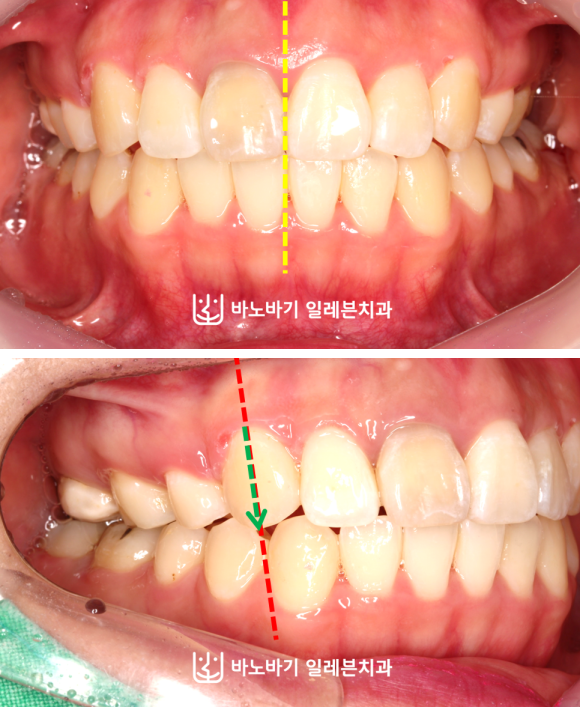

이렇게 무턱교정이 끝났습니다. 전치부 개방교합을 해소하여 앞니가 닿을 수 있게 됐고, 중심선 불일치도 해결했습니다.

우측 치열도 교합을 맞춰서 정상적인 모습으로 치아가 맞물리도록 만들었습니다. 그만큼 저작기능도 좋아졌죠.

마찬가지로 상악 두 곳에 발치하여 공간을 만든 다음, 코티코토미 시술로 잇몸뼈를 훨씬 유연한 상태로 만든 후 치아를 훨씬 더 큰 폭으로 움직이는 데에 성공했습니다.

이렇게 하악 총생을 개선하고, 앞니를 조금 더 넣었습니다. 그래서 위와 같이 입술 돌출이 어느 정도는 개선되었습니다.

입을 충분히 자연스럽게 다물 수 있도록 만들었지요. 하지만 측면 안모에서는 변화에 한계가 있었습니다.

그래서 턱끝수술을 받으셨는데요. 아래턱에 볼륨감이 살아나면서 옆모습에 입체감이 생겼습니다.

환자분께서도 이렇게 달라진 외모에 만족스러워하셨습니다.